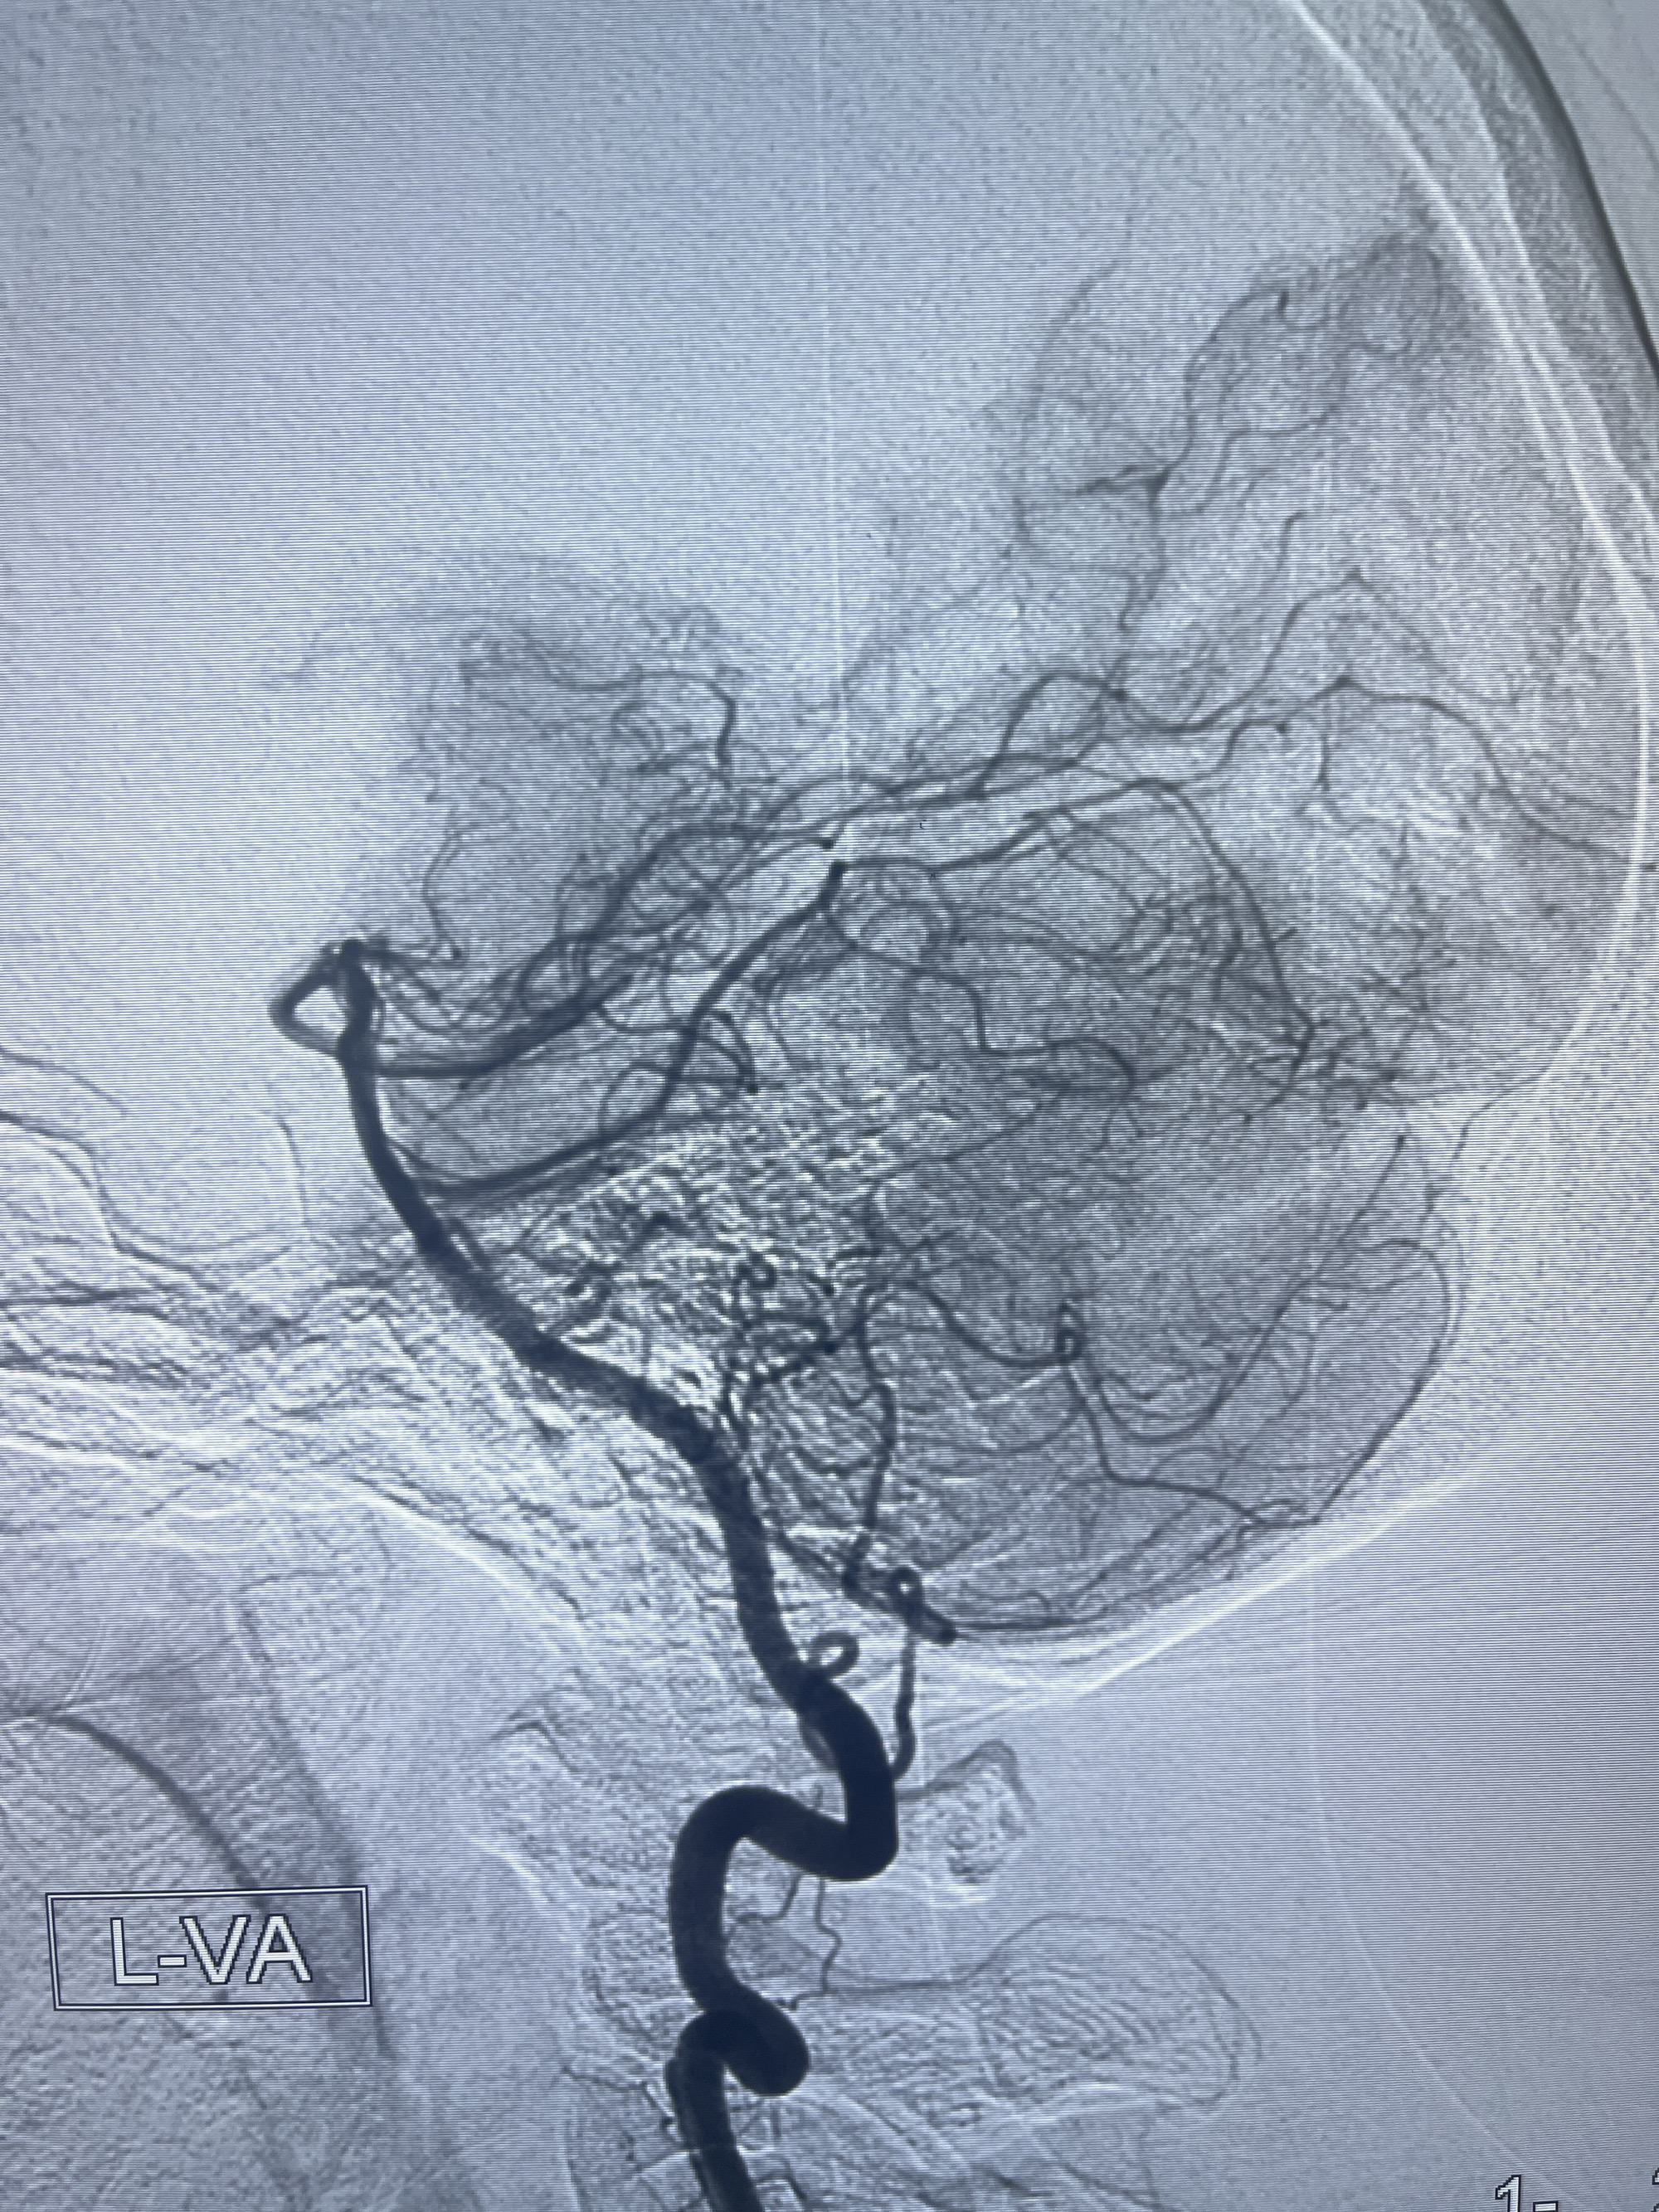

202.04.28脑血管造影:右侧大脑后动脉远段闭塞,右侧椎动脉V4段可见“囊状造影剂填充影”,大小7.64*7.65mm,可见PICA由动脉瘤发出;